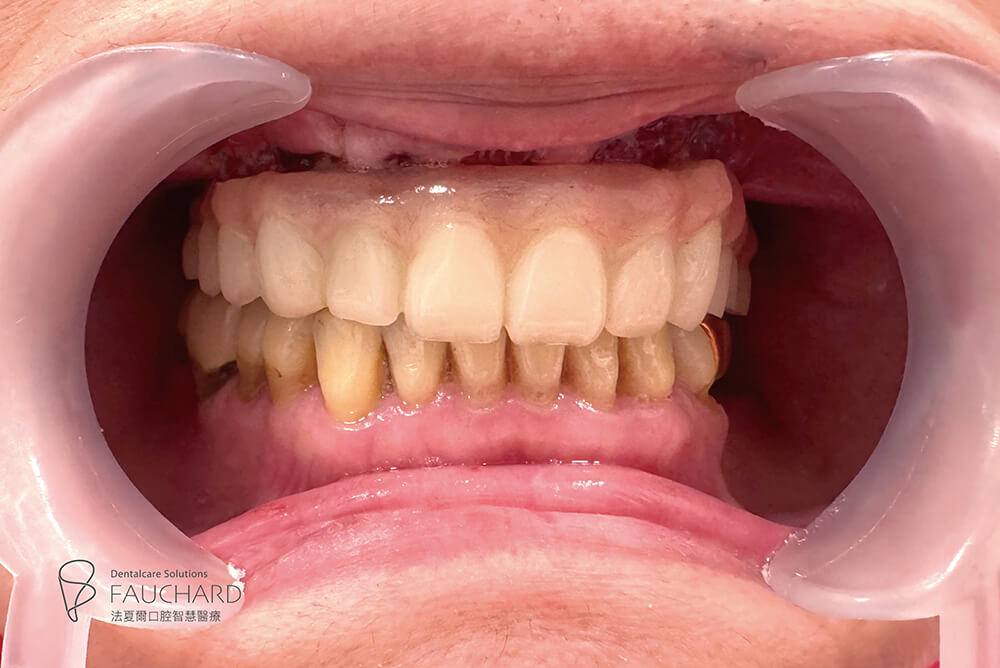

● 口腔狀況:上顎無牙

● 治療時間:當天有牙

● 植體數量:4 根

● 假牙類型:上顎、整座固定假牙

● 植體數量:6 根